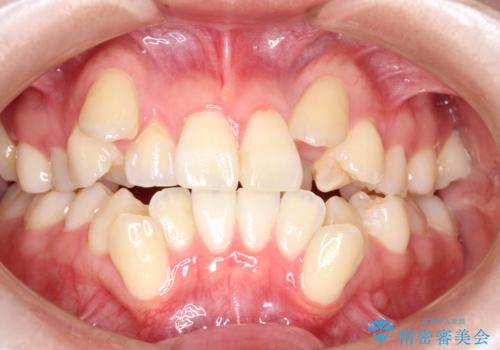

【ワイヤー矯正】八重歯 歯のでこぼこを治したい!

下顎前歯の叢生を短期間で改善

担当医 河口智英